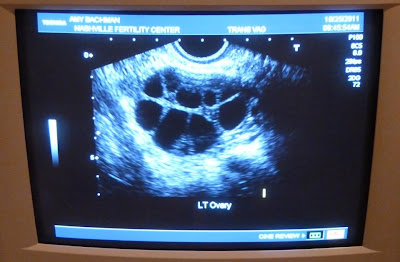

| Screen shot of a few of the follicles on my left ovary. Looks like a honeycomb, right? |

Tonight, at 11 p.m. I will have 2 injections of hCG (Ovidrel) -- 1 entire syringe and the other just 1/2. This is called the "trigger shot". It is timed precisely to coincide with the final maturation of the follicles. When this shot is given, those follicles release their eggs.